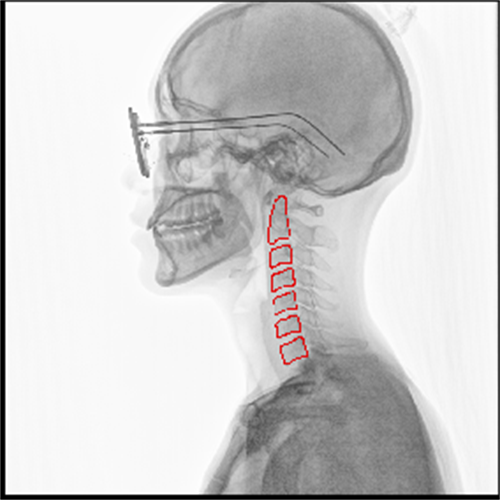

③功能化。当然随着未来对疾病的诊断以及预后评估,功能化发展必然是DR的发展趋势。在肺功能上的应用,可以通过测量呼吸流速、流量分析、肺部通气功能分析等,直观的展现出患者呼吸过程中的通气异常区域,对通气异常及COPD患者提供影像学诊断全新的技术手段。对肺部进行血流灌注分析,来实现在无造影剂条件下对肺栓塞进行评估。还可以应用于骨骼运动方向研究,例如颈椎运动功能成像,骨折修复后愈合状态的评估等。(左边第一张图为肺部血流灌注成像,右边两张图为颈椎运动功能成像)